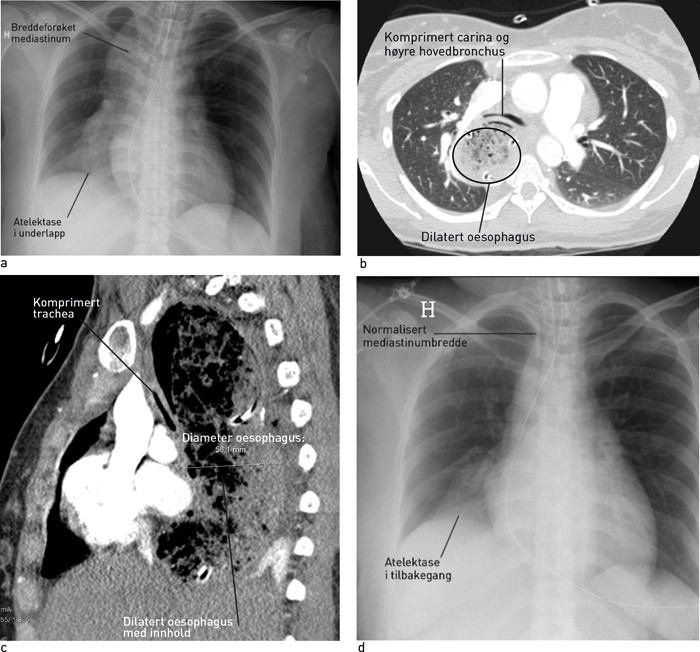

En kvinne i 30-årene ble innlagt på sykehus for fødsel. De tre siste årene hadde hun hatt tiltakende dysfagi av væske og fast føde, dyspné i forbindelse med måltider og vanskeligheter med å rape. Fødselen forløp ukomplisert, men to dager post partum fikk hun akutt respirasjonsbesvær etter frokost og måtte intuberes. Røntgen thorax front viste økt bredde på øvre mediastinum og høyresidig underlappsatelektase (fig 1a). Videre utredning med CT thorax viste betydelig dilatasjon av hele oesophagus og at denne komprimerte både trachea og høyre hovedbronchus (fig 1b, fig 1c).

Gastroskopi viste dilatert oesophagus med matrester, men ingen strikturer eller slimhinneforandringer. På mistanke om akalasi ble det umiddelbart foretatt blokking av nedre oesophagussfinkter med ballong. Kontrollrøntgen samme kveld viste normalisert mediastinumbredde og delvis tilbakegang av underlappsatelektasen (fig 1d). Ved kontroll to uker senere var pasienten symptomfri, og oesophagusmanometri viste funn forenlig med akalasi.